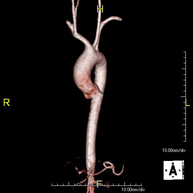

Prueba diagnóstica no invasiva que consiste en el estudio de la arteria aorta abdominal, obteniendo imágenes de alta definición anatómica mediante el empleo de un campo electromagnético y ondas de radio (con un emisor y un receptor). Es indispensable el uso de contraste paramagnético (Gadolinio). Sin embargo, no utiliza radiación ionizante. La calidad de las imágenes permite realizar reconstrucciones en 2D y 3D. Está indicado en aquellos pacientes con enfermedad vascular (aterosclerosis), estudio de aneurismas, en estudios pre-quirúrgicos de lesiones adyacentes a la aorta abdominal como "mapa" vascular, etc. - Angio RM Aorta-ilíaca

Prueba diagnóstica no invasiva que consiste en el estudio de la arteria aorta abdominal de las arterias ilíacas, obteniendo imágenes de alta definición anatómica mediante el empleo de un campo electromagnético y ondas de radio (con un emisor y un receptor). Es indispensable el uso de contraste paramagnético (Gadolinio). Sin embargo, no utiliza radiación ionizante. La calidad de las imágenes permite realizar reconstrucciones en 2D y 3D. Esta prueba está especialmente indicada como estudio pre-quirúrgico (mapa vascular) antes de intervenciones percutáneas o quirúrgicas de aorta abdominal y arterias ilíacas, estudio complementario en pacientes con isquemia de miembros inferiores, etc. - Angio RM Arterial extremidades inferiores

Prueba diagnóstica no invasiva que consiste en el estudio de la arteria aorta abdominal, obteniendo imágenes de alta definición anatómica mediante el empleo de un campo electromagnético y ondas de radio (con un emisor y un receptor). Es indispensable el uso de contraste intravenoso paramagnético (gadolinio). Sin embargo, no utiliza radiación ionizante. La calidad de las imágenes permite realizar reconstrucciones en 2D y 3D. Está indicado en aquellos pacientes con enfermedad vascular (aterosclerosis), estudio de aneurismas, en estudios pre-quirúrgicos de lesiones adyacentes a la aorta abdominal como "mapa" vascular… - Angio-RM Aorta iliaca

Prueba diagnóstica no invasiva que consiste en el estudio de la arteria aorta abdominal, obteniendo imágenes de alta definición anatómica mediante el empleo de un campo electromagnético y ondas de radio (con un emisor y un receptor). Es indispensable el uso de contraste intravenoso paramagnético (gadolinio). Sin embargo, no utiliza radiación ionizante. La calidad de las imágenes permite realizar reconstrucciones en 2D y 3D. Esta prueba está especialmente indicada como estudio pre-quirúrgico (mapa vascular) antes de intervenciones percutáneas o quirúrgicas de aorta abdominal, estudio complementario en pacientes con isquemia de miembros inferiores… - Angio-RM Arterias renales